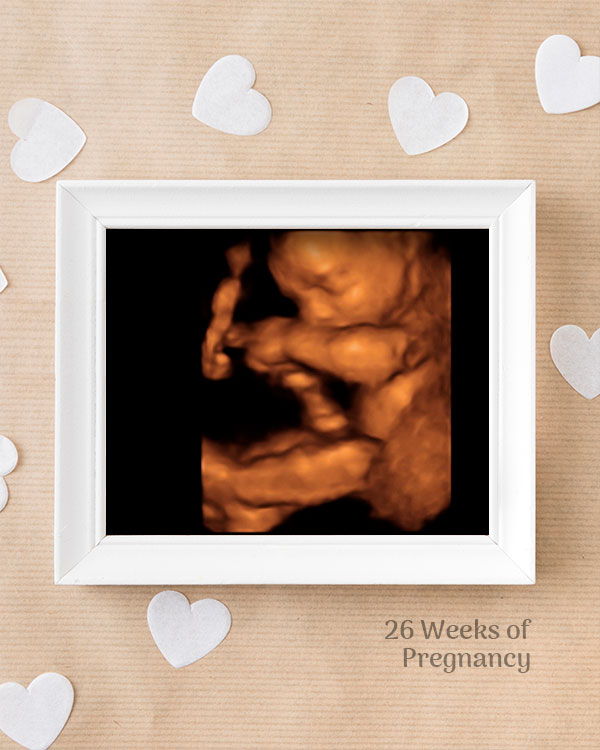

3D / 4D Baby Scan

Mediserv Diagnostics pioneered 4D scanning in the Malabar region. These advanced scans provide realistic images of the baby, allowing detailed evaluation of fetal structures and movements while creating a meaningful bonding experience for parents.